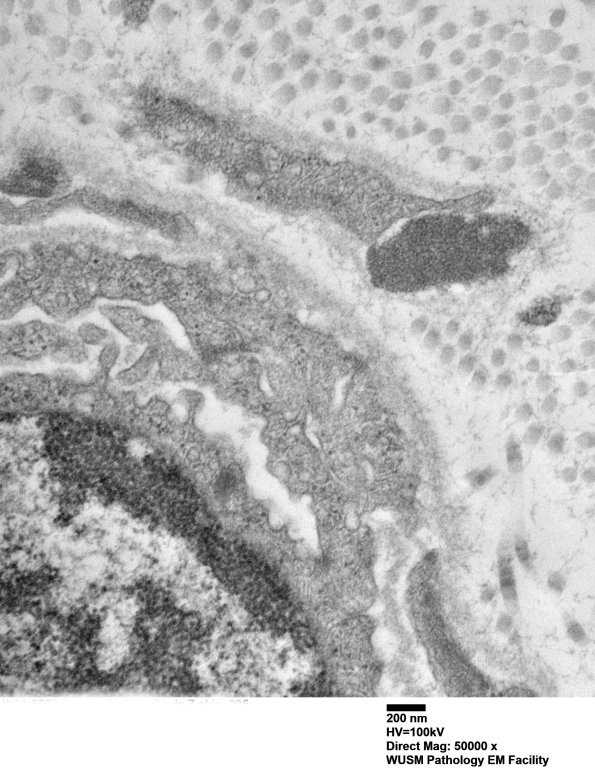

11E2B A small vessel and GOM. (electron micrograph)